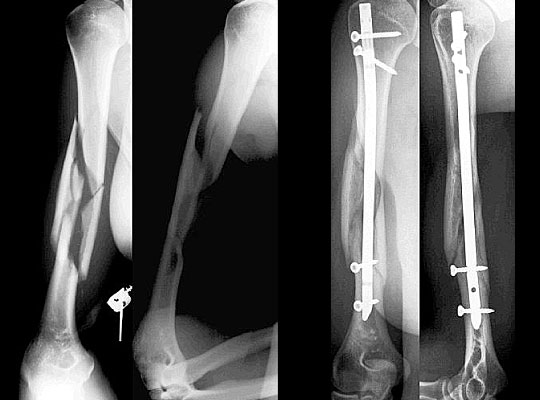

Parçalı kırıklar, aynı uzuvda birden fazla kırık, karşı kol kırığı bulunması, çoklu organ yaralanmaları gibi durumlarda cerrahi tespit ile kırığın kaynatılması gerekir. Kırık tespiti için, plak-vida, kanal içi çivi ya da dıştan tespit cihazı uygulanabilir.

Kanal içi çivileme sınırlı girişimsel olmakla birlikte, omuz ya da dirsek eklemine yakın girişi nedeniyle bu alanlarda hasara yol açabilmektedir. Plak-vida uygulamaları açık cerrahinin avantaj ve dezavantajlarını barındırır.

Dıştan tespit cihazları ise, çoklu yaralanmaların ya da açık kırıkların ilk müdahalesi olup kalıcı tedavi için genellikle tercih edilmemektedir.